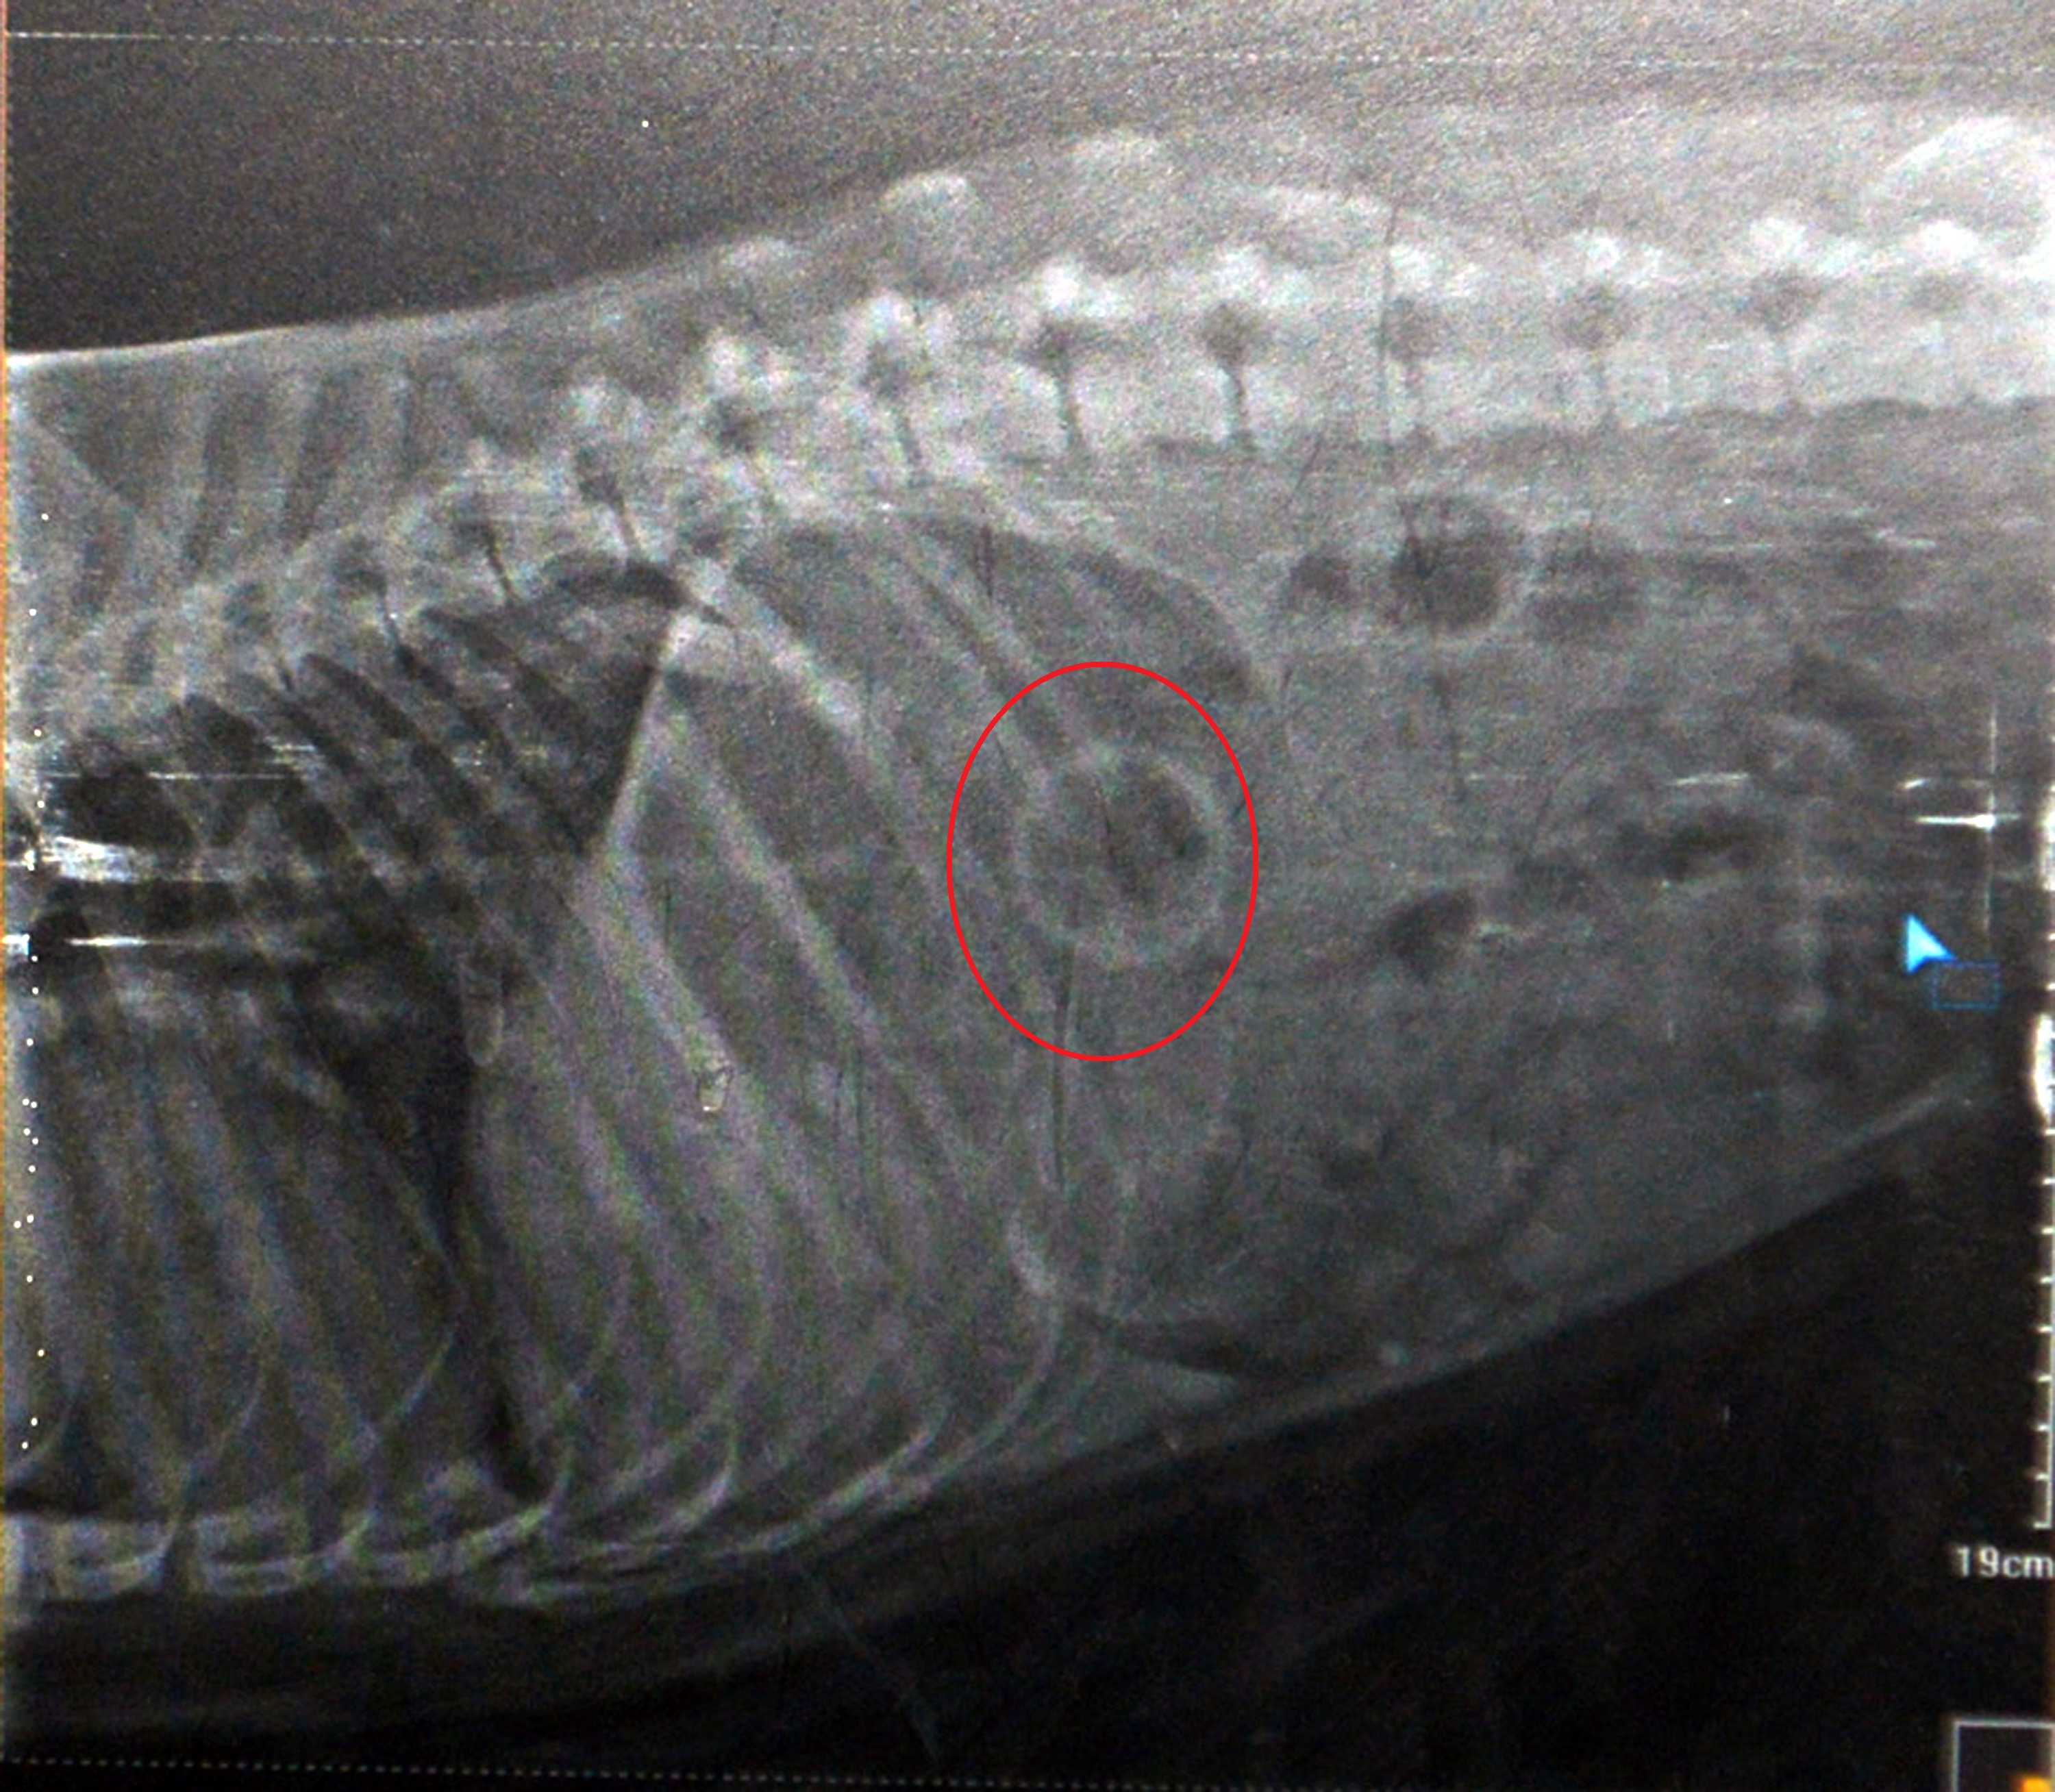

Veteriner hekim Mete Betin tarafından mide röntgeni çekilen Bella, topun yerinin tespit edilmesinin ardından ameliyat edildi. Operasyon sonrası Bella’nın midesindeki top çıkarıldı.

Ameliyatı yapan veteriner hekim, zor operasyon olduğunu, 45 dakika sürdüğünü ve sonucun başarılı olduğunu söyledi.

Bella’nın midesindeki topu cerrahi müdahaleyle çıkardığını belirterek “Sağlığı iyi durumda. Tabii bir süre sıvı beslenmesi gerekiyor. Sonra normal hayatına dönecek. Bu tür durumlarda yutulan cisim bağırsakları tıkarsa ölüme neden olabilir. Evcil hayvan sahiplerinin dikkatli olması lazım. Hızlı müdahale çok önemli. Hayvanların yutamayacakları büyük toplarla vakit geçirmelerine izin verilmelidir. Yutabilecekleri cisimleri onlardan uzak tutmalıyız” diye konuştu.